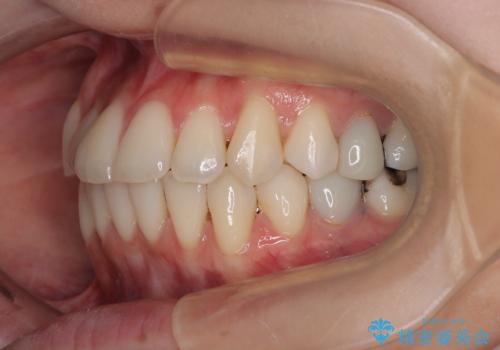

- 上下前歯のデコボコとクロスバイトを気にして来院された患者様です。

治療済みの処置歯が多いため、インビザラインを用いて矯正治療を行うこととしました。

下顎臼歯部にブリッジが装着されており、移動不可のため、IPR(歯と歯の間を削る)と歯列全体を拡大させることで、歯並びを整えていくこととしました。

インビザライン特有の奥歯の噛みにくさが治療後半に発現しましたが、無事に終了させることができました。